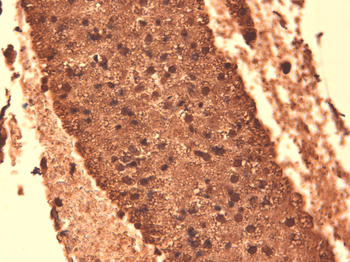

Immunohistochemical staining of paraffin embedded mouse brain tissue using anti-NIS (2.5 ug/ml)